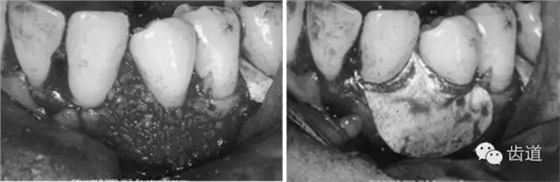

病損區(qū)常規(guī)行牙周翻瓣術(shù),去除感染的牙周袋內(nèi)壁上皮和肉芽組織,根面和骨面清創(chuàng)后,根據(jù)骨缺損和牙根外形選擇并修剪屏障膜,使之能完全覆蓋病損面并固定之,然后齦瓣復(fù)位嚴(yán)密縫合。

3、手術(shù)切口設(shè)計(jì)

需根據(jù)手術(shù)目的、預(yù)后、美觀效果等綜合平衡決定,可根據(jù)患者和病損區(qū)實(shí)際情況靈活選擇溝內(nèi)切口、內(nèi)斜切口、保留齦乳頭切口等,但要注意以盡量保留較多的角化牙齦組織為原則,也即要盡量多保留牙齦乳頭,以保證術(shù)后牙齦能覆蓋膜材料,避免外露導(dǎo)致感染、炎癥等。尤其在鄰面牙間隙處應(yīng)盡量選用齦乳頭保存術(shù)。一般應(yīng)做縱切口和在根方做松弛切口,以保證齦瓣能充分移動(dòng)和避免過(guò)大的張力。

4、膜材料的選擇